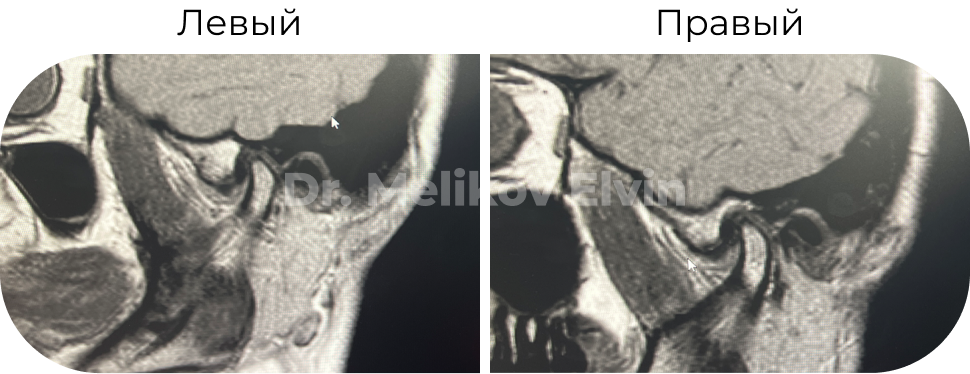

Например, если уже имеются предпосылки к дВНЧС, определяется дискомфорт, щелчки или хрусты — нужно обязательно провести диагностику суставов в виде МРТ.